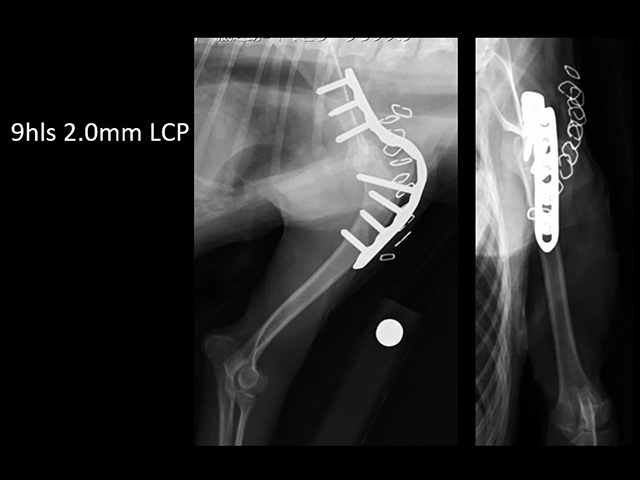

また、肩関節を形成する骨の形成異常が関与している場合には、プレートを使用した肩関節固定術(※)を行います。